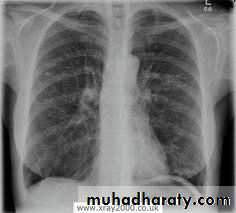

• CXR

• CT scan

thoracic surgery